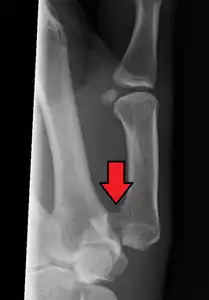

In the case of the Bennett fracture, the proximal metacarpal fragment remains attached to the anterior oblique ligament, which in turn is attached to the tubercle of the trapezium bone of the CMC joint. This ligamentous attachment ensures that the proximal fragment remains in its correct anatomical position.

The distal fragment of the first metacarpal bone possesses the majority of the articular surface of the first CMC joint. Unlike the proximal fracture fragment, strong ligaments and muscle tendons of the hand tend to pull this fragment out of its correct anatomical position.

Specifically:

- tension from the abductor pollicis longus muscle (APL) subluxates the fragment in a dorsal, radial, and proximal direction

- tension from the APL rotates the fragment into supination

- tension from the adductor pollicis muscle (ADP) displaces the metacarpal head into the palm

Tension from the APL and ADP muscles frequently leads to displacement of the fracture fragments, even in cases where the fracture fragments are initially in their proper anatomic position. Because of the aforementioned biomechanical features, Bennett fractures nearly always require some form of intervention to ensure healing in the correct anatomical position and restoration of proper function of the thumb CMC joint.